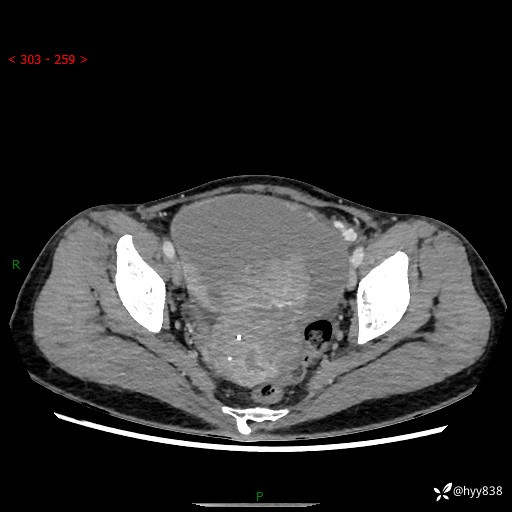

【患者信息】:女,50岁

【主诉】:外院超声发现腹盆肿块,为进一步诊治来我院,门诊已“盆腔肿块”收入院。

腹盆CT平扫+增强

【临床诊断】:盆腔肿瘤